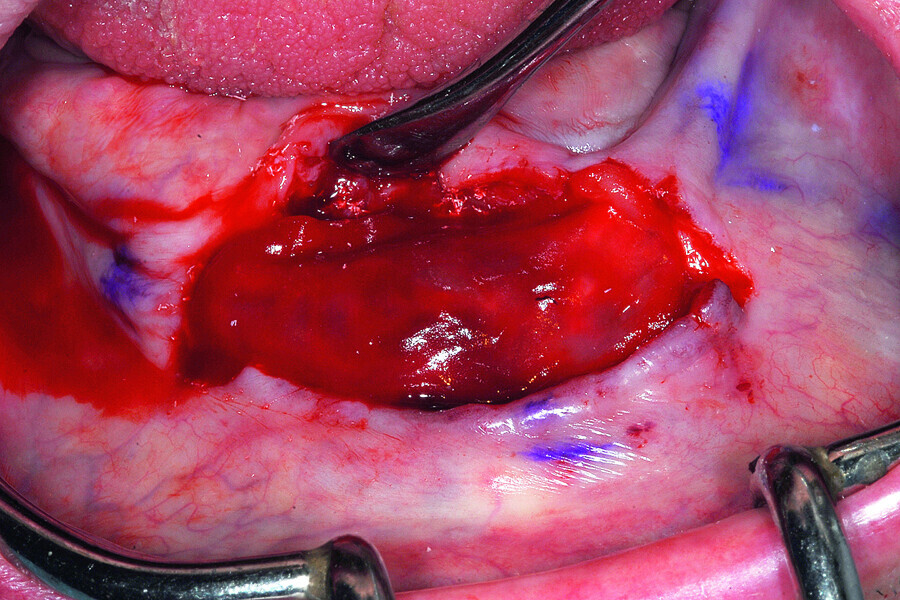

Fig. 13: A full thickness mucoperiosteal flap exposed the knifeedged ridge of the mandibular symphysis.